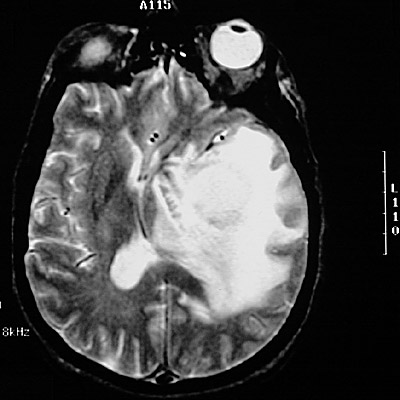

This T2 weighted MRI scan reveals a

cerebral abscess

caused by infection with Aspergillus that is obscured by the bright fluid of the

adjacent marked edema

.